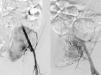

La paciente es una mujer de 19 años que consultó por algias pélvicas en su hospital de referencia. Se practicó una ecografía abdominal que halló una masa sólida, única de 8cm localizada en fosa iliaca izquierda, sospechosa de teratoma ovárico. Es intervenida quirúrgicamente objetivándose uno órganos genitales internos normales y una tumoración sólida retroperitoneal, sobre el paquete vascular iliaco izquierdo, íntimamente adherida a él, decidiéndose el cierre de la laparotomía y la derivación a nuestro centro. En nuestro centro, se practicó un examen analítico completo que incluía una bioquímica completa, hemograma y coagulación que fueron normales. Se practicó una TAC torácica, abdominal y pélvica que informó de la presencia de una masa pélvica única en región pélvica con un tamaño de 9 x 7 x 6cm, con pequeñas calcificaciones lineales difusas y sin infiltración de estructuras vecinas (fig. 1). La lesión estaba ampliamente vascularizada, objetivándose un paso precoz del contraste intravenoso desde su aporte arterial al territorio venoso sistémico. Se practicó una arteriografía que dibujó el aporte vascular arterial de la lesión, formado por ramas procedentes de las arterias iliaca externa e interna, procediéndose a la realización de una embolización arterial de la misma (fig. 2) como paso previo a la extirpación quirúrgica que se realizó asociando una linfadenectomía pélvica del territorio iliaco izquierdo. La paciente fue dada de alta sin incidencias en el 6.° día postoperatorio. El análisis definitivo de la pieza y de los ganglios linfáticos remitidos descartó la naturaleza sarcomatosa de la lesión y confirmó el diagnóstico de CE unicéntrica hialinovascular sin afectación de ninguno de los 19 ganglios remitidos. La paciente se encuentra libre de enfermedad un año después de la cirugía.